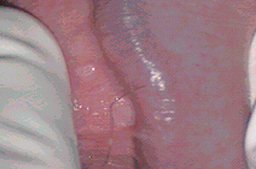

• Lesiones planas por VPH en pene